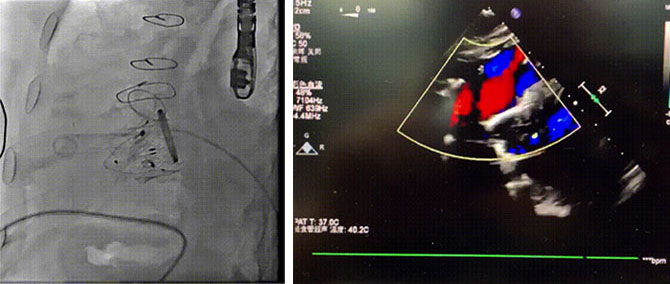

手术全程在经食道心脏彩超(TEE)和数字减影血管造影(DSA)的指引下进行。全麻后,郭惠明、刘健团队在患者右侧颈静脉穿刺,采用静脉入路将输送器送入右心,在进入右室后释放室间隔锚定装置,旋转输送器,使得锚定装置对准室间隔面。而后释放前瓣夹持件,确定夹持件位于右室侧,释放人工瓣膜盘片,再使用DSA和超声确认盘片位置,同时调整瓣膜的同轴性。紧接着在DSA和超声的监视下调整室间隔锚定件贴合室间隔,释放室间隔锚定装置。再次确认瓣膜的稳定性和同轴性后,释放瓣膜并将输送器撤出体内,最终完成LuX-Valve Plus三尖瓣人工瓣膜植入(图2-5)。手术获得圆满成功。患者在手术室即刻拔除气管插管,术后超声提示:人工三尖瓣瓣膜同轴性良好,瓣架固定牢靠,无反流和瓣周漏。

图4 术后DSA 图5 术后超声